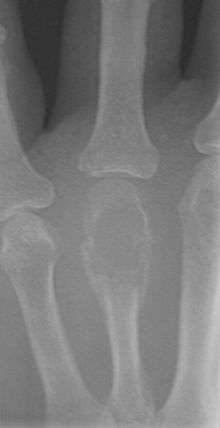

A bone tumor (also spelled bone tumour) is a neoplastic growth of tissue in bone. Abnormal growths found in the bone can be either benign (noncancerous) or malignant (cancerous).

Primary tumors of bone can be divided into benign tumors and cancers. Common benign bone tumors may be neoplastic, developmental, traumatic, infectious, or inflammatory in etiology. Some benign tumors are not true neoplasms, but rather, represent hamartomas, namely the osteochondroma. The most common locations for many primary tumors, both benign and malignant include the distal femur and proximal tibia (around the knee joint).

Examples of benign bone tumors include osteoma, osteoid osteoma, osteochondroma, osteoblastoma, enchondroma, giant cell tumor of bone, aneurysmal bone cyst, and fibrous dysplasia of bone.

Malignant primary bone tumors include osteosarcoma, chondrosarcoma, Ewing's sarcoma, fibrosarcoma, and other types.